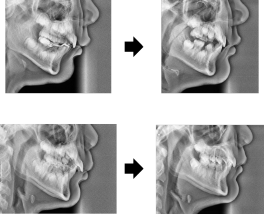

이렇게 헤드기어를 진행하여 교정을 진행한 환자의 모습입니다.

무턱으로 인해 돌출되어 보였던게 많이 좋아졌습니다.